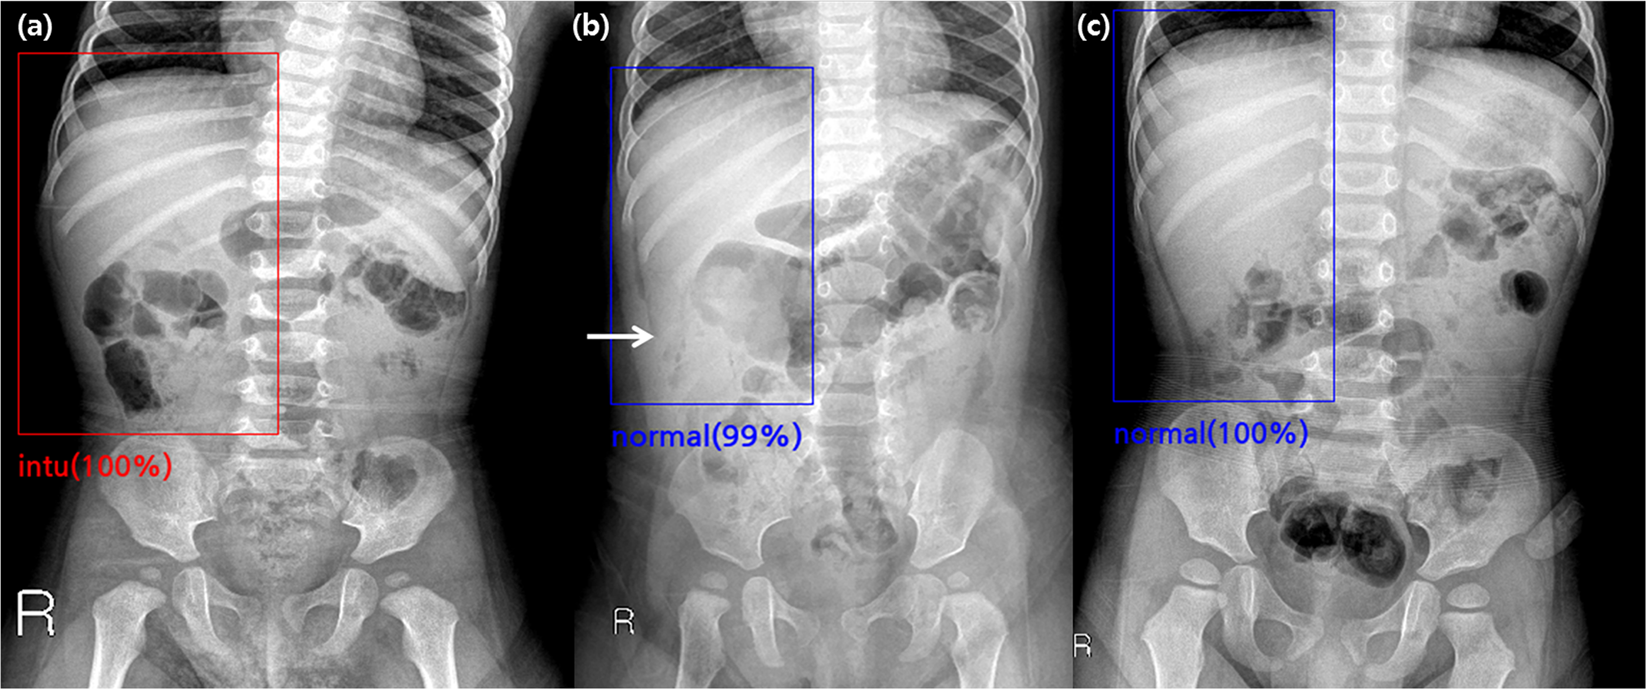

Figure 3

False-positive and false-negative cases found by the algorithm in the validation set. (a) A supine abdominal radiograph of a 15-month-old boy without intussusception. One radiologist and the algorithm reported false-positive results, while the other three radiologists reported true-negative results. (b) A supine abdominal radiograph of a 10-month-old boy with intussusception. One radiologist and the algorithm reported false-negative results, while the other three radiologists reported true-positive results. (c) A supine abdominal radiograph of a 29-month-old boy with intussusception. All of the four radiologists and the algorithm reported false-negative results.